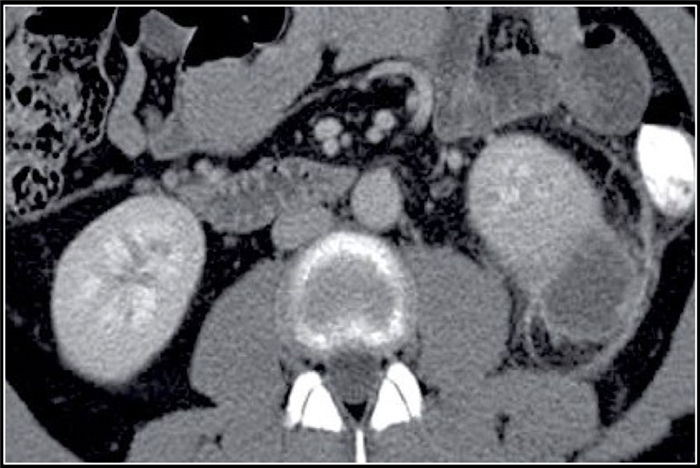

(Слева) КТ с контрастированием, аксиальная проекция: выявлена увеличенная правая почка с множественными скоплениями жидкости неправильной формы, не накапливающими контраст. Данные признаки характерны для многоочаговых абсцессов.

(Справа) КТ с контрастированием, аксиальная проекция: выявлены многокамерные абсцессы почки с ободковым контрастированием и абсцессы околопочечного пространства.